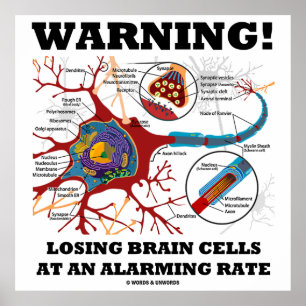

Varning! Förlorade hjärnceller med en alarmerande Poster

Pris1 533,00 kr